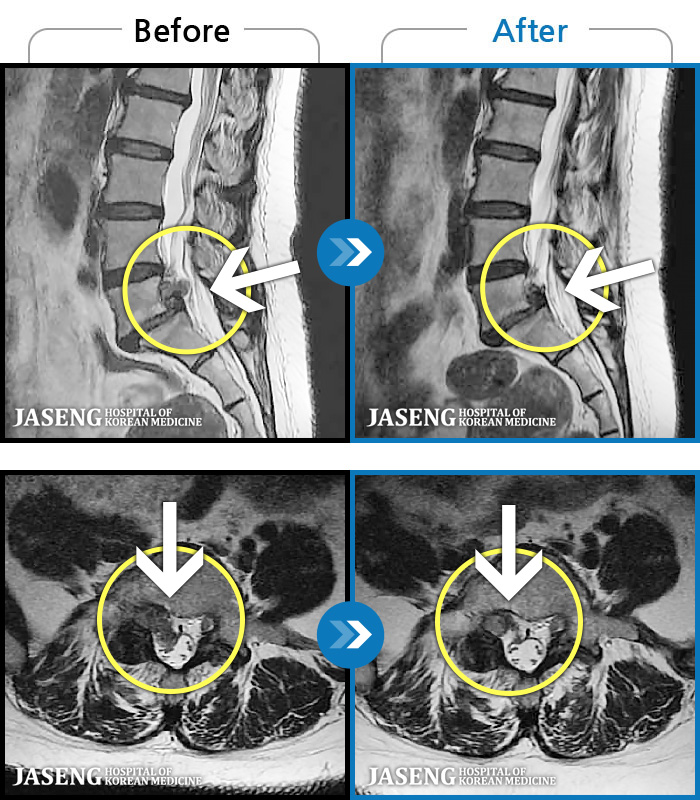

[ؿ] 24.10.10~25.04.23